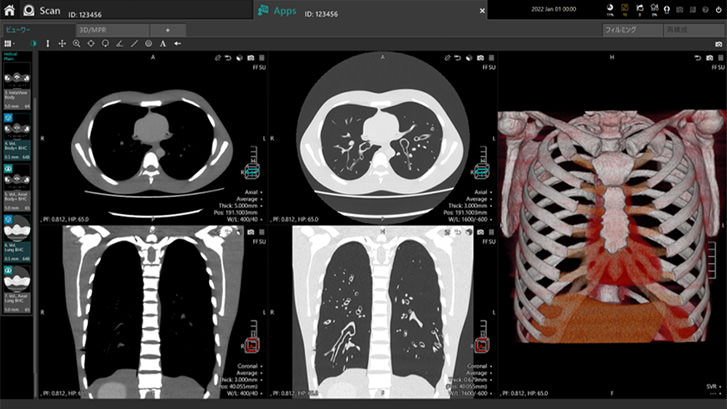

撮影終了後はデータを選択するだけで、部位や検査種別ごとにあらかじめ設定しておいたレイアウトで画像を表示させることができるなど、確認作業の効率も向上しました。27インチの大画面で画像を確認することが可能になったことに加え、撮影が終了したらすぐに検査の種類や部位に適した断面像や3D画像を確認できます。特に一刻を争う救急医療では、技師の画像処理を待たずに医師が結果を参照して処置に進めることができるのは、大きなメリットです。

シンプルで使いやすいインターフェースの説明画像

画像を確認したいデータを選択

プリセットしたレイアウトに自動で画像を表示